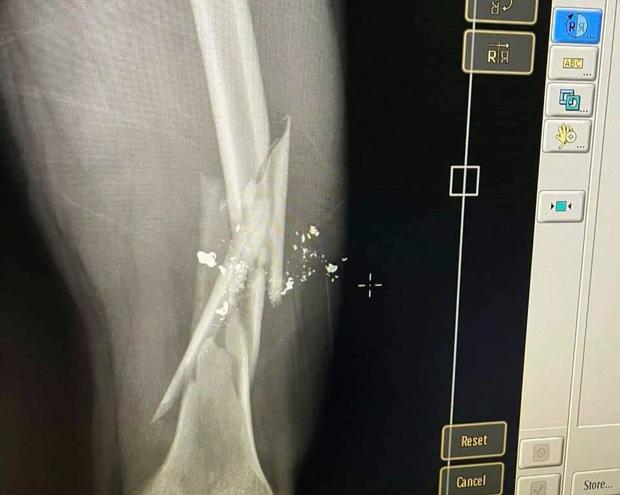

Phần đùi nạn nhân bị gãy sau khi bị Hòa dùng súng bắn

Sau khi thanh toán xong, cả nhóm ra khỏi quán rồi đứng lại tiếp tục nói chuyện. Do bức xúc vì bị đấm vào miệng khi còn ở trong quán, Hòa đã xách súng bắn anh Giang dẫn đến gãy xương đùi. Nạn nhân sau đó được đưa đi bệnh viện cấp cứu.